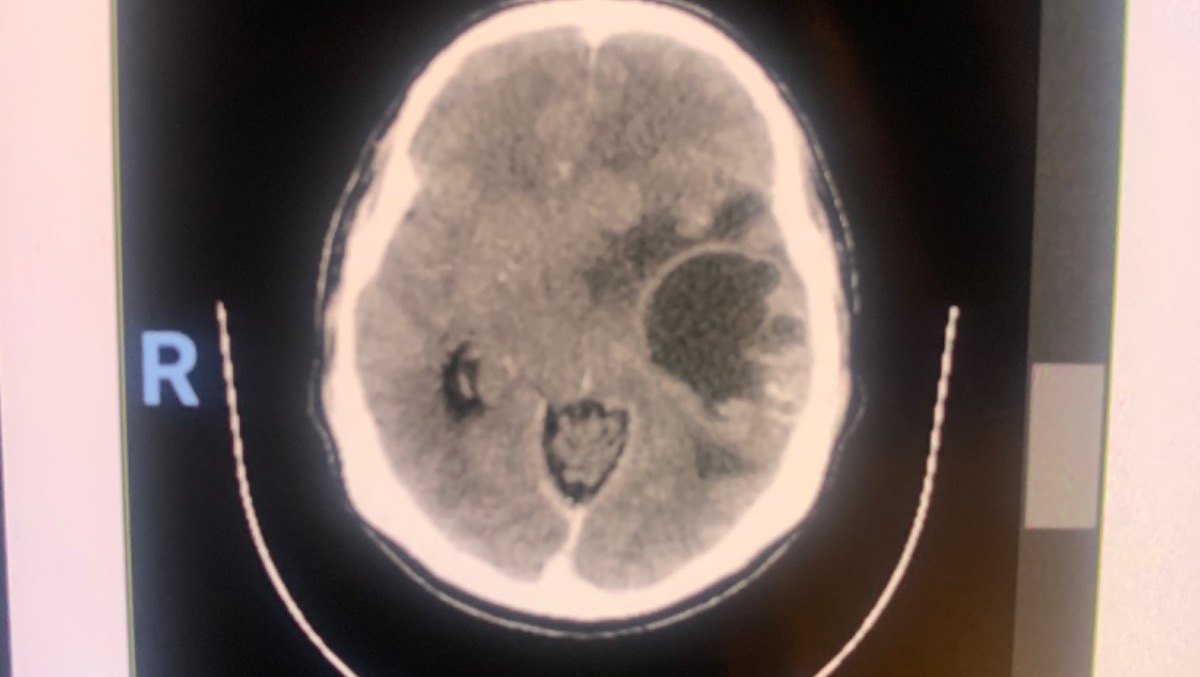

In addition, Diana revealed that he also has other types of brain damage that continue affecting his body which haven’t been diagnosed.

Broca’s aphasia is a condition that hampers the ability to communicate, and is located in the front lobe of the brain, the area that controls the body’s movements.

It should be noted that a big-sized brain tumor was recently detected, which is why he needs a surgery that costs around 15,000 dollars.